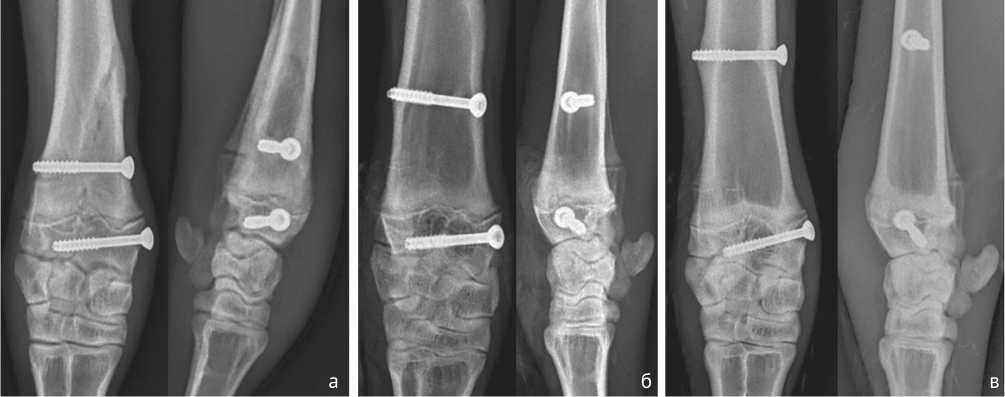

Рентгенологически признаки сращения перелома регистрировали к 30-ым суткам после операции. Отмечали участки полного восстановления корковой пластинки. Линия остеотомии эпифиза и суставной поверхности была заполнена новообразованной костной тканью. Линия суставной поверхности была анатомически правильная, участков наслоений и разрастаний не отмечали. Высота суставной щели — равномерная на всем протяжении. Пластинка роста непрерывна, в проекции линии остеотомии не имела участков оссификации (рис. 1, а). К 120-ым суткам линия остеотомии не визуализировалась. Суставная поверхность не имела патологических образований. Суставная щель хорошо просматривалась. Пластинка роста была открыта. Деформации суставной поверхности не отмечали (рис. 1, б). На завершающем этапе (365 суток после операции) на рентгенограммах регистрировали полную перестройку кости в зоне остеотомии. Суставные поверхности лучезапястного сустава имели анатомически правильные контуры. Патологических изменений костных структур не выявлено (рис. 1, в).

Рис. 1. Рентгенограммы ягненка в прямой и боковой проекции: а — на 30-ые сутки фиксации; б — на 120-ые сутки фиксации; в — на 365-ые сутки фиксации